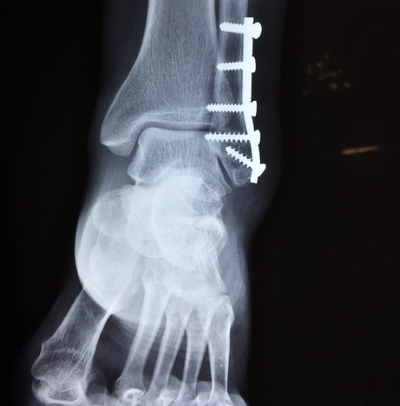

마지막으로 3단계 염좌는 인대가 완전히 파열된 상태로, 극심한 통증과 함께 심한 부종, 멍, 그리고 발목 관절의 불안정성이 두드러집니다. 발목에 체중을 싣기 어렵고, 심한 경우 '뚝' 하는 파열음을 들었을 수도 있습니다.